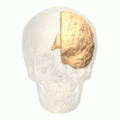

![]() Medial surface of left cerebral hemisphere. (Cuneus visible at left in red.) | |

Position of cuneus(red) of left cerebral hemisphere.

The cuneus (Latin for "wedge"; plural, cunei) is a smaller lobe in the occipital lobe of the brain. The cuneus is bounded anteriorly by the parieto-occipital sulcus, inferiorly by the calcarine sulcus.